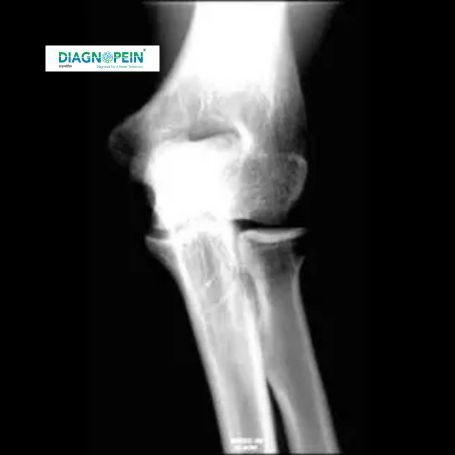

CT Right Elbow Joint (Plain) scan is an advanced imaging test designed to capture detailed cross-sectional images of the bones, ligaments, and surrounding soft tissues of the right elbow joint. At Diagnopein Nashik, this scan helps doctors precisely evaluate injuries, trauma, fractures, or abnormalities that may not be clearly visible through standard X-rays.

Using high-resolution computed tomography (CT) technology, the scan generates three-dimensional images that enable accurate visualization of joint alignment, bone density, and potential joint space narrowing. The non-invasive nature and quick results make it a vital diagnostic tool for orthopedic and sports-related conditions.

The CT Right Elbow Joint scan plays a crucial role in detecting internal bone or joint complications when clinical examination or X-rays are insufficient. In Nashik, where an active lifestyle often leads to elbow stress in sports or physical work, early imaging ensures timely treatment and recovery.